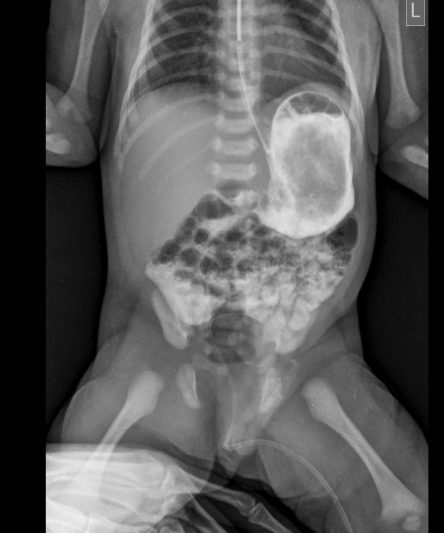

Microskan with Ultra high frequency can take the Lateral Lumbar Spine image of a 90 kg Patient with the correct image receptor